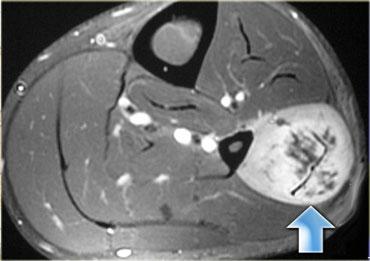

Hoại tử cơ vôi hóa là một tình trạng hiếm gặp sau chấn thương, đặc trưng bởi sự hình thành muộn của một khối vôi hóa loạn dưỡng, xảy ra hầu như độc quyền ở chi dưới.

Trong hoại tử cơ vôi hóa, toàn bộ một cơ đơn lẻ bị thay thế bởi một khối hình thoi với phần trung tâm hóa lỏng và vôi hóa ngoại vi.

Chúng có thể biểu hiện như các khối mô mềm ngày càng to lên với các đặc điểm lâm sàng gợi ý một khối u mô mềm đang phát triển hoặc nhiễm trùng.